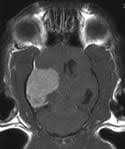

Brain Tumors In Cats Petmd from www.petmd.com In the sections below, we look at several types of brain tumor and their specific symptoms however, signs that a headache could be a symptom of a brain tumor include: A tumor forms when cells divide abnormally and rapidly. Brain tumours in dogs and cats are unfortunately as common as they are in people. Since there's limited space within the skull, signs and symptoms of a brain tumor typically develop when abnormal tissue expands and destroys or pushes on healthy brain tissue, the tissue around the. Symptoms may arise because of impairment tumors in the upper regions of the brain may also affect the brainstem if they cause pressure resulting in brain tissue herniating (getting pushed). This allows doctors to see inside the body without cutting it open and the procedures is commonly used to find problems inside the skull, such as brain tumors or signs of a stroke. Overall, seizures are a more common sign of a brain tumor in dogs, while behavior change is more common in cats. After taking note of clinical signs and conducting basic blood work, your vet performs an ultrasound or magnetic resonance imaging on your cat's head to diagnose a brain.

After taking note of clinical signs and conducting basic blood work, your vet performs an ultrasound or magnetic resonance imaging on your cat's head to diagnose a brain.